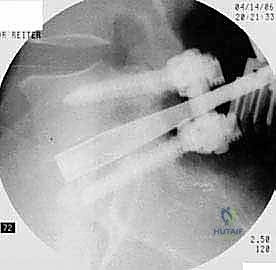

يتم وضع المريض على بطنه. يتم عمل شق جراحي دقيق في أسفل الظهر. باستخدام أجهزة الملاحة الجراحية والأشعة السينية الحية (Fluoroscopy)، يتم تحديد المستويات الفقرية المستهدفة بدقة.

الخطوة 4: زراعة القفص والطعم العظمي (Cage Insertion)

يتم إدخال قفص مصنوع من مادة PEEK أو التيتانيوم، مملوء بطعم عظمي (يؤخذ غالباً من المريض نفسه أو طعم صناعي)، في المساحة الفارغة. هذا القفص يعيد الارتفاع الطبيعي للفقرات ويخفف الضغط عن منافذ الأعصاب.